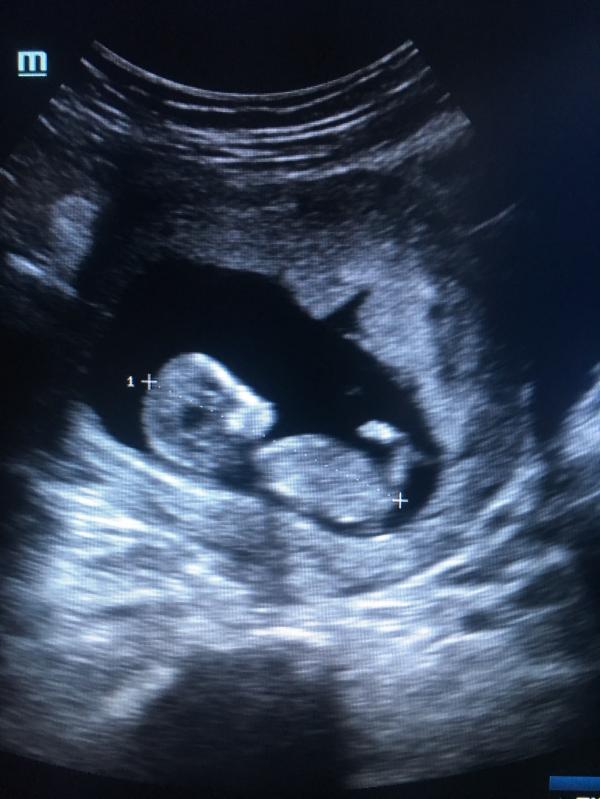

Фотография с ножкой очень мило😍а где делали УЗИ?)

Спасибо😍в женской консультации в поликлиники